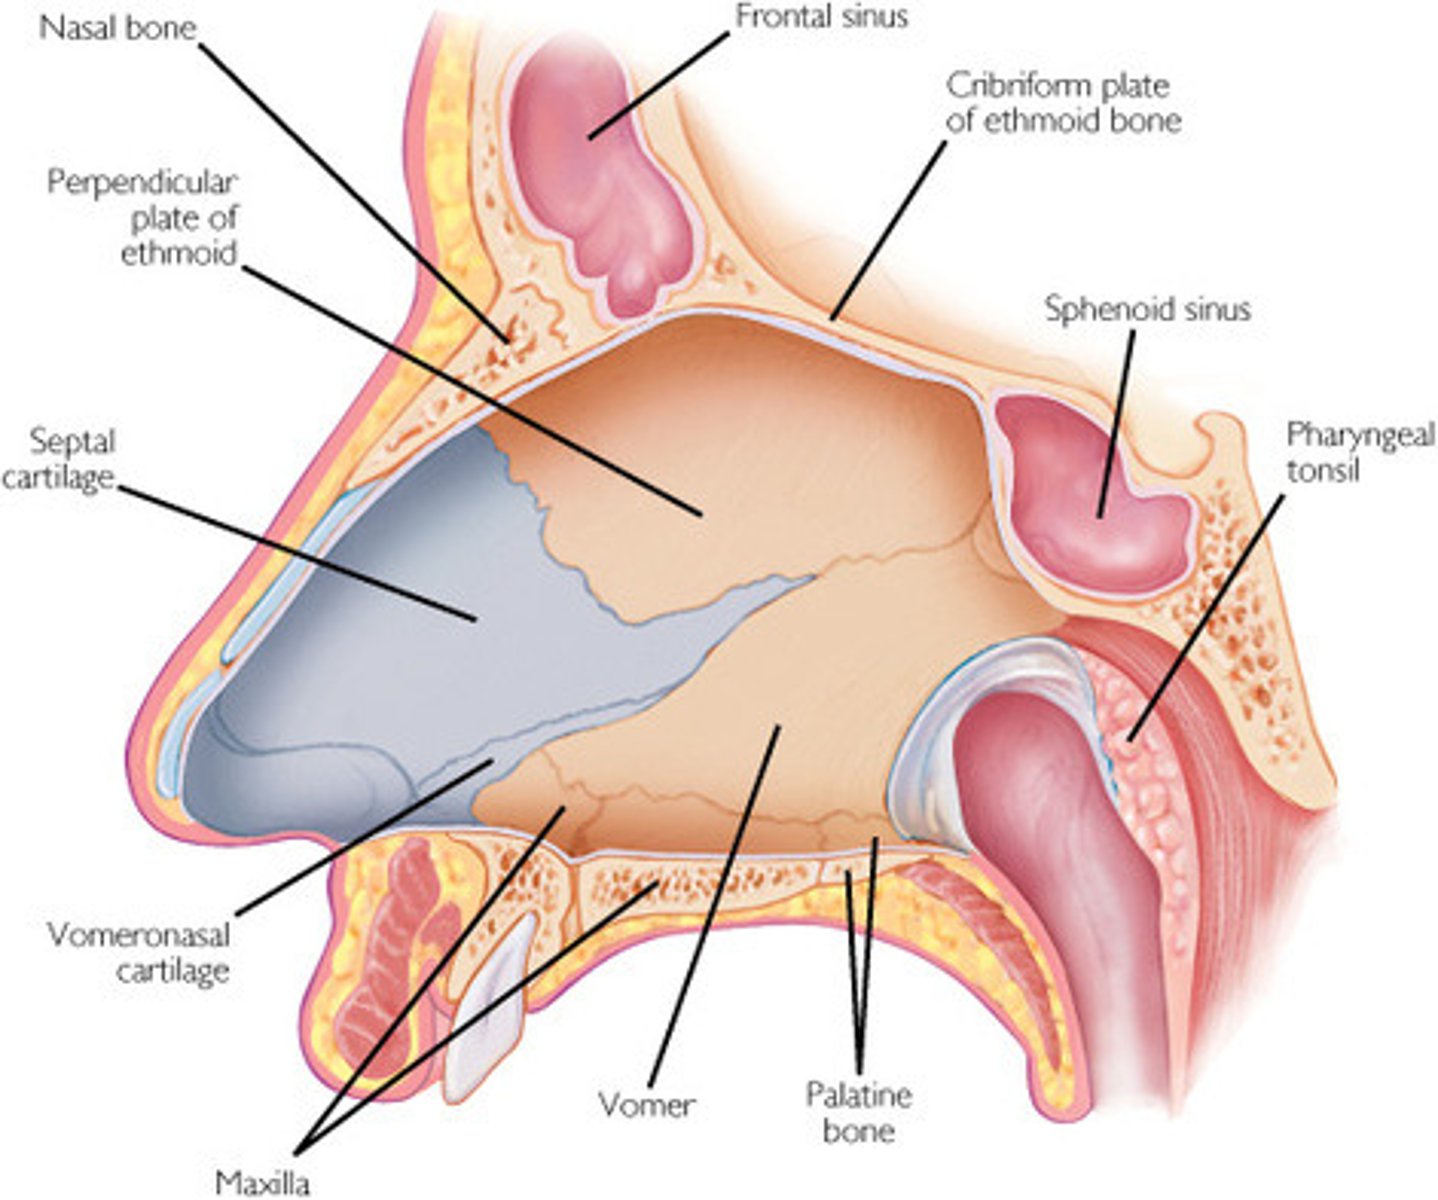

os ethmoidale

akytkaulis

Lamina cribrosa

Akytoji plokštelė

Sinus sphenoidalis

pleištakaulio antis

Concha nasalis

Nosies kriauklės

maxilla, ae f

viršutinis žandikaulis

sinus maxillaris

Viršutinio žandikaulio antis

Vomer

Noragas

Cavitas nasi

nosies ertmė